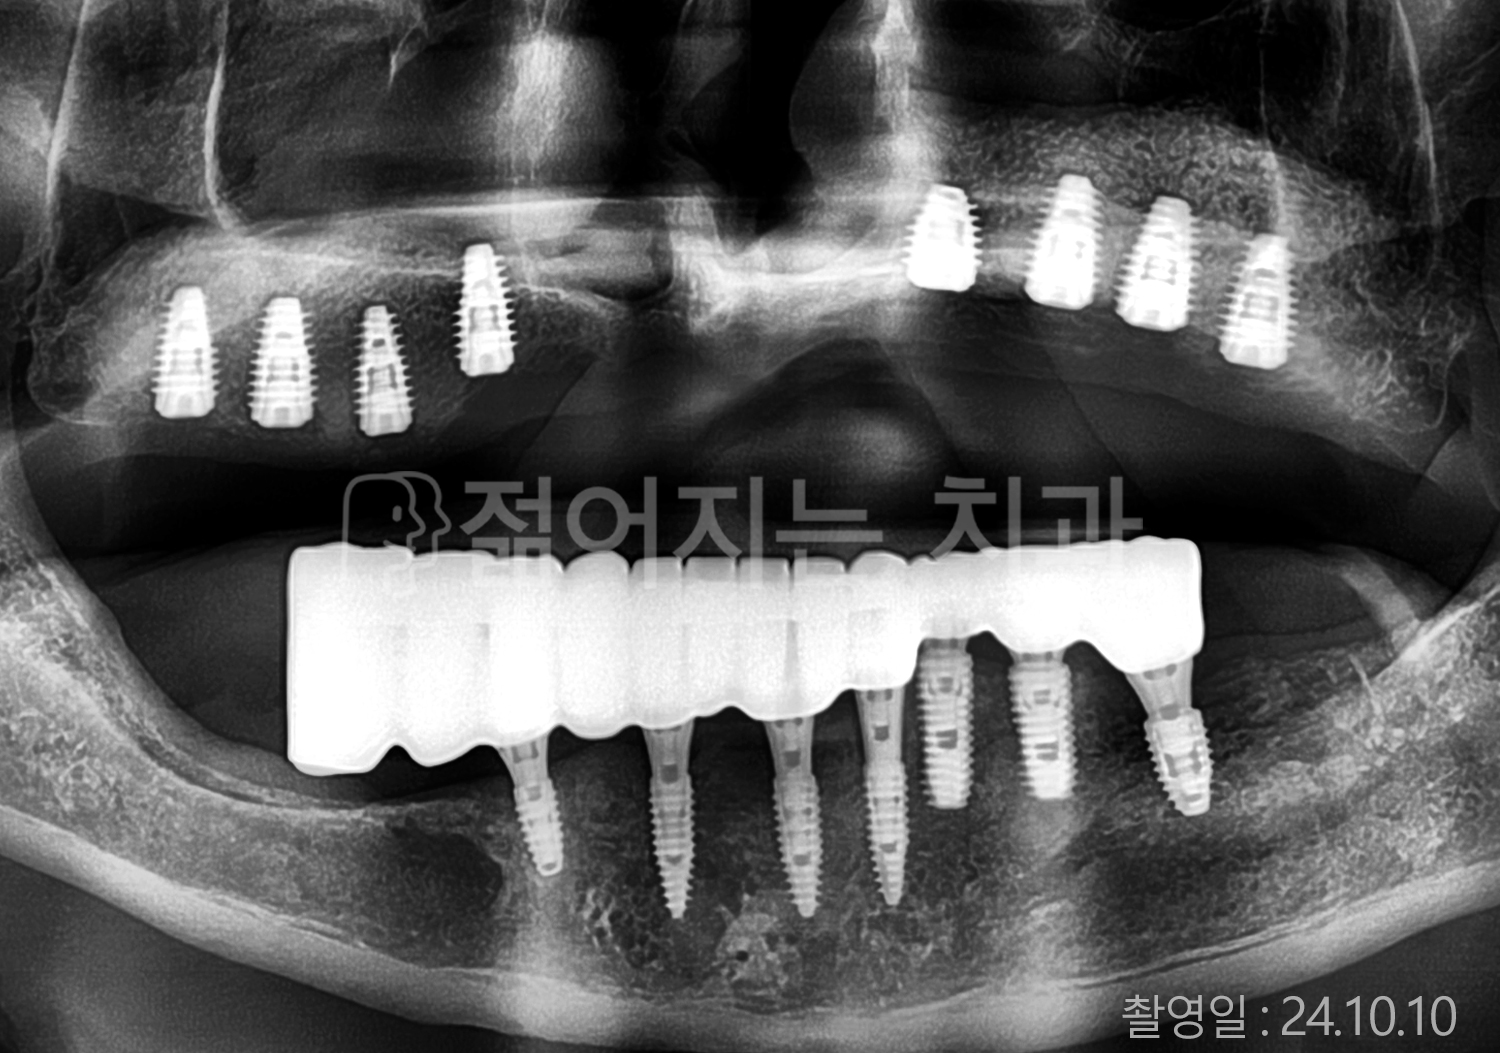

• 80대 전체치아 10개 이상 임플란트

• 60대 고혈압, 당뇨, 고지혈증 전체치아 10개 이상 임플란트

• 60대 전체치아 10개 이상 임플란트

• 60대 고혈압, 고지혈증 전체치아 10개 이상 임플란트

• 50대 고혈압, 당뇨, 고지혈증 전체치아 10개 이상 임플란트

• 70대 골다골증, 파킨스병 전체치아 10개 이상 임플란트

• 40대 전체치아 10개 이상 임플란트

• 60대 골다골증 전체치아 10개 이상 임플란트

• 40대 고혈압 전체치아 10개 이상 임플란트

• 50대 전체치아 10개 이상 임플란트

• 70대 전체치아 10개 이상 임플란트